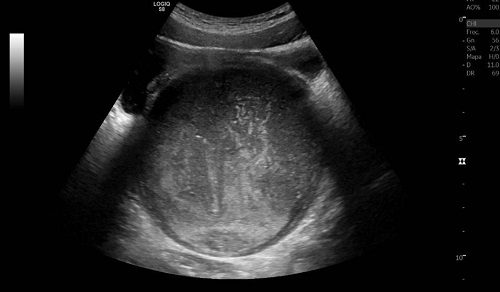

A la exploración presenta dolor abdominal con palpación de masa abdominal en región hipogástrica. Tacto rectal con dedil de guante limpio, sin palpación de fecaloma, con abombamiento de la pared anterior. Ante el fracaso del tratamiento oral y la retención de orina se administra enema rectal, que resulta inicialmente efectivo, realizando deposición y micción abundante. Presenta mejoría inicial, pero sin resolución del completa, por lo que se solicita ecografía abdominal, observándose masa de contenido hemático de 14 cm retrovesical, compatible con hematocolpos (Figura 1). Valorada por Ginecología, realizan himenectomía por himen imperforado, extrayéndose 900 ml de contenido hemático, con resolución completa del cuadro de dolor abdominal.

Figura 1. Imagen ecográfica de la masa compatible con hematocolpos